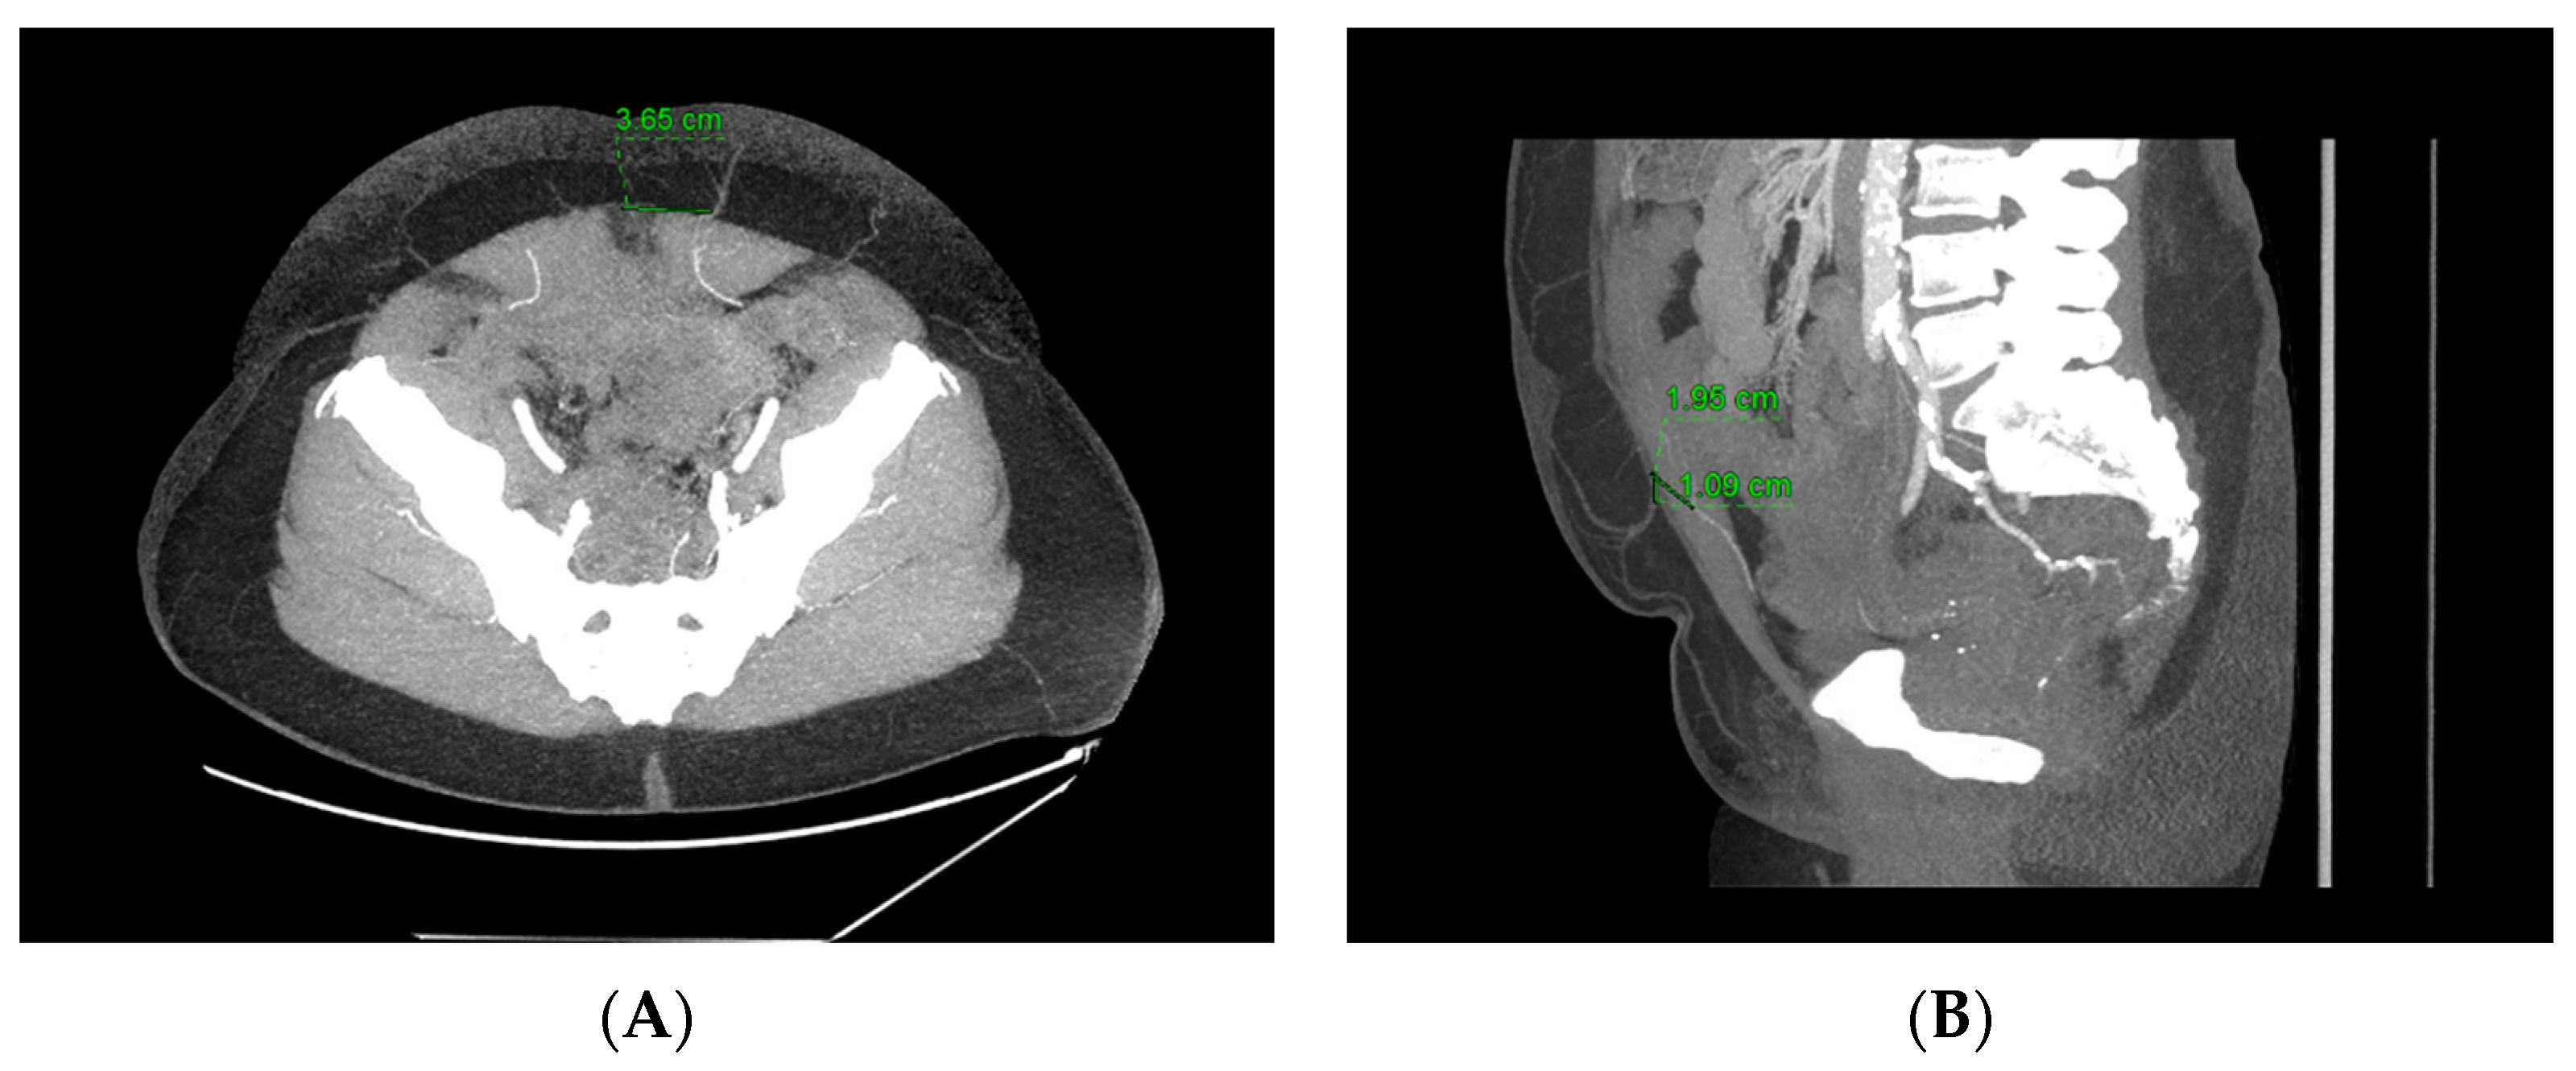

3. Computed Tomography Angiography (CTA)